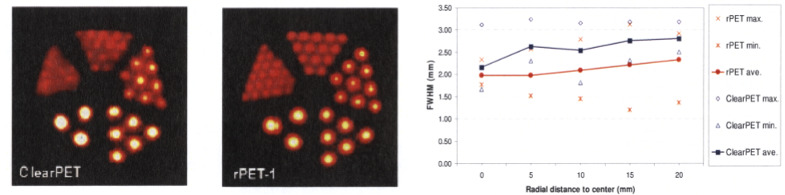

It is usually difficult to compare different designs of Positron Emission Tomography (PET) small-animal scanners because of the disparity of measurements protocols. In this work we compare two commercial PET scanners installed at CIEMAT (Madrid, Spain): the ClearPET and the rPET-1, using an assessment procedure that fulfilled the recommendations of the new NEMA NU 4-2008 standard to evaluate small animal PET systems, including spatial resolution, sensitivity, scatter fraction and count losses studies. |